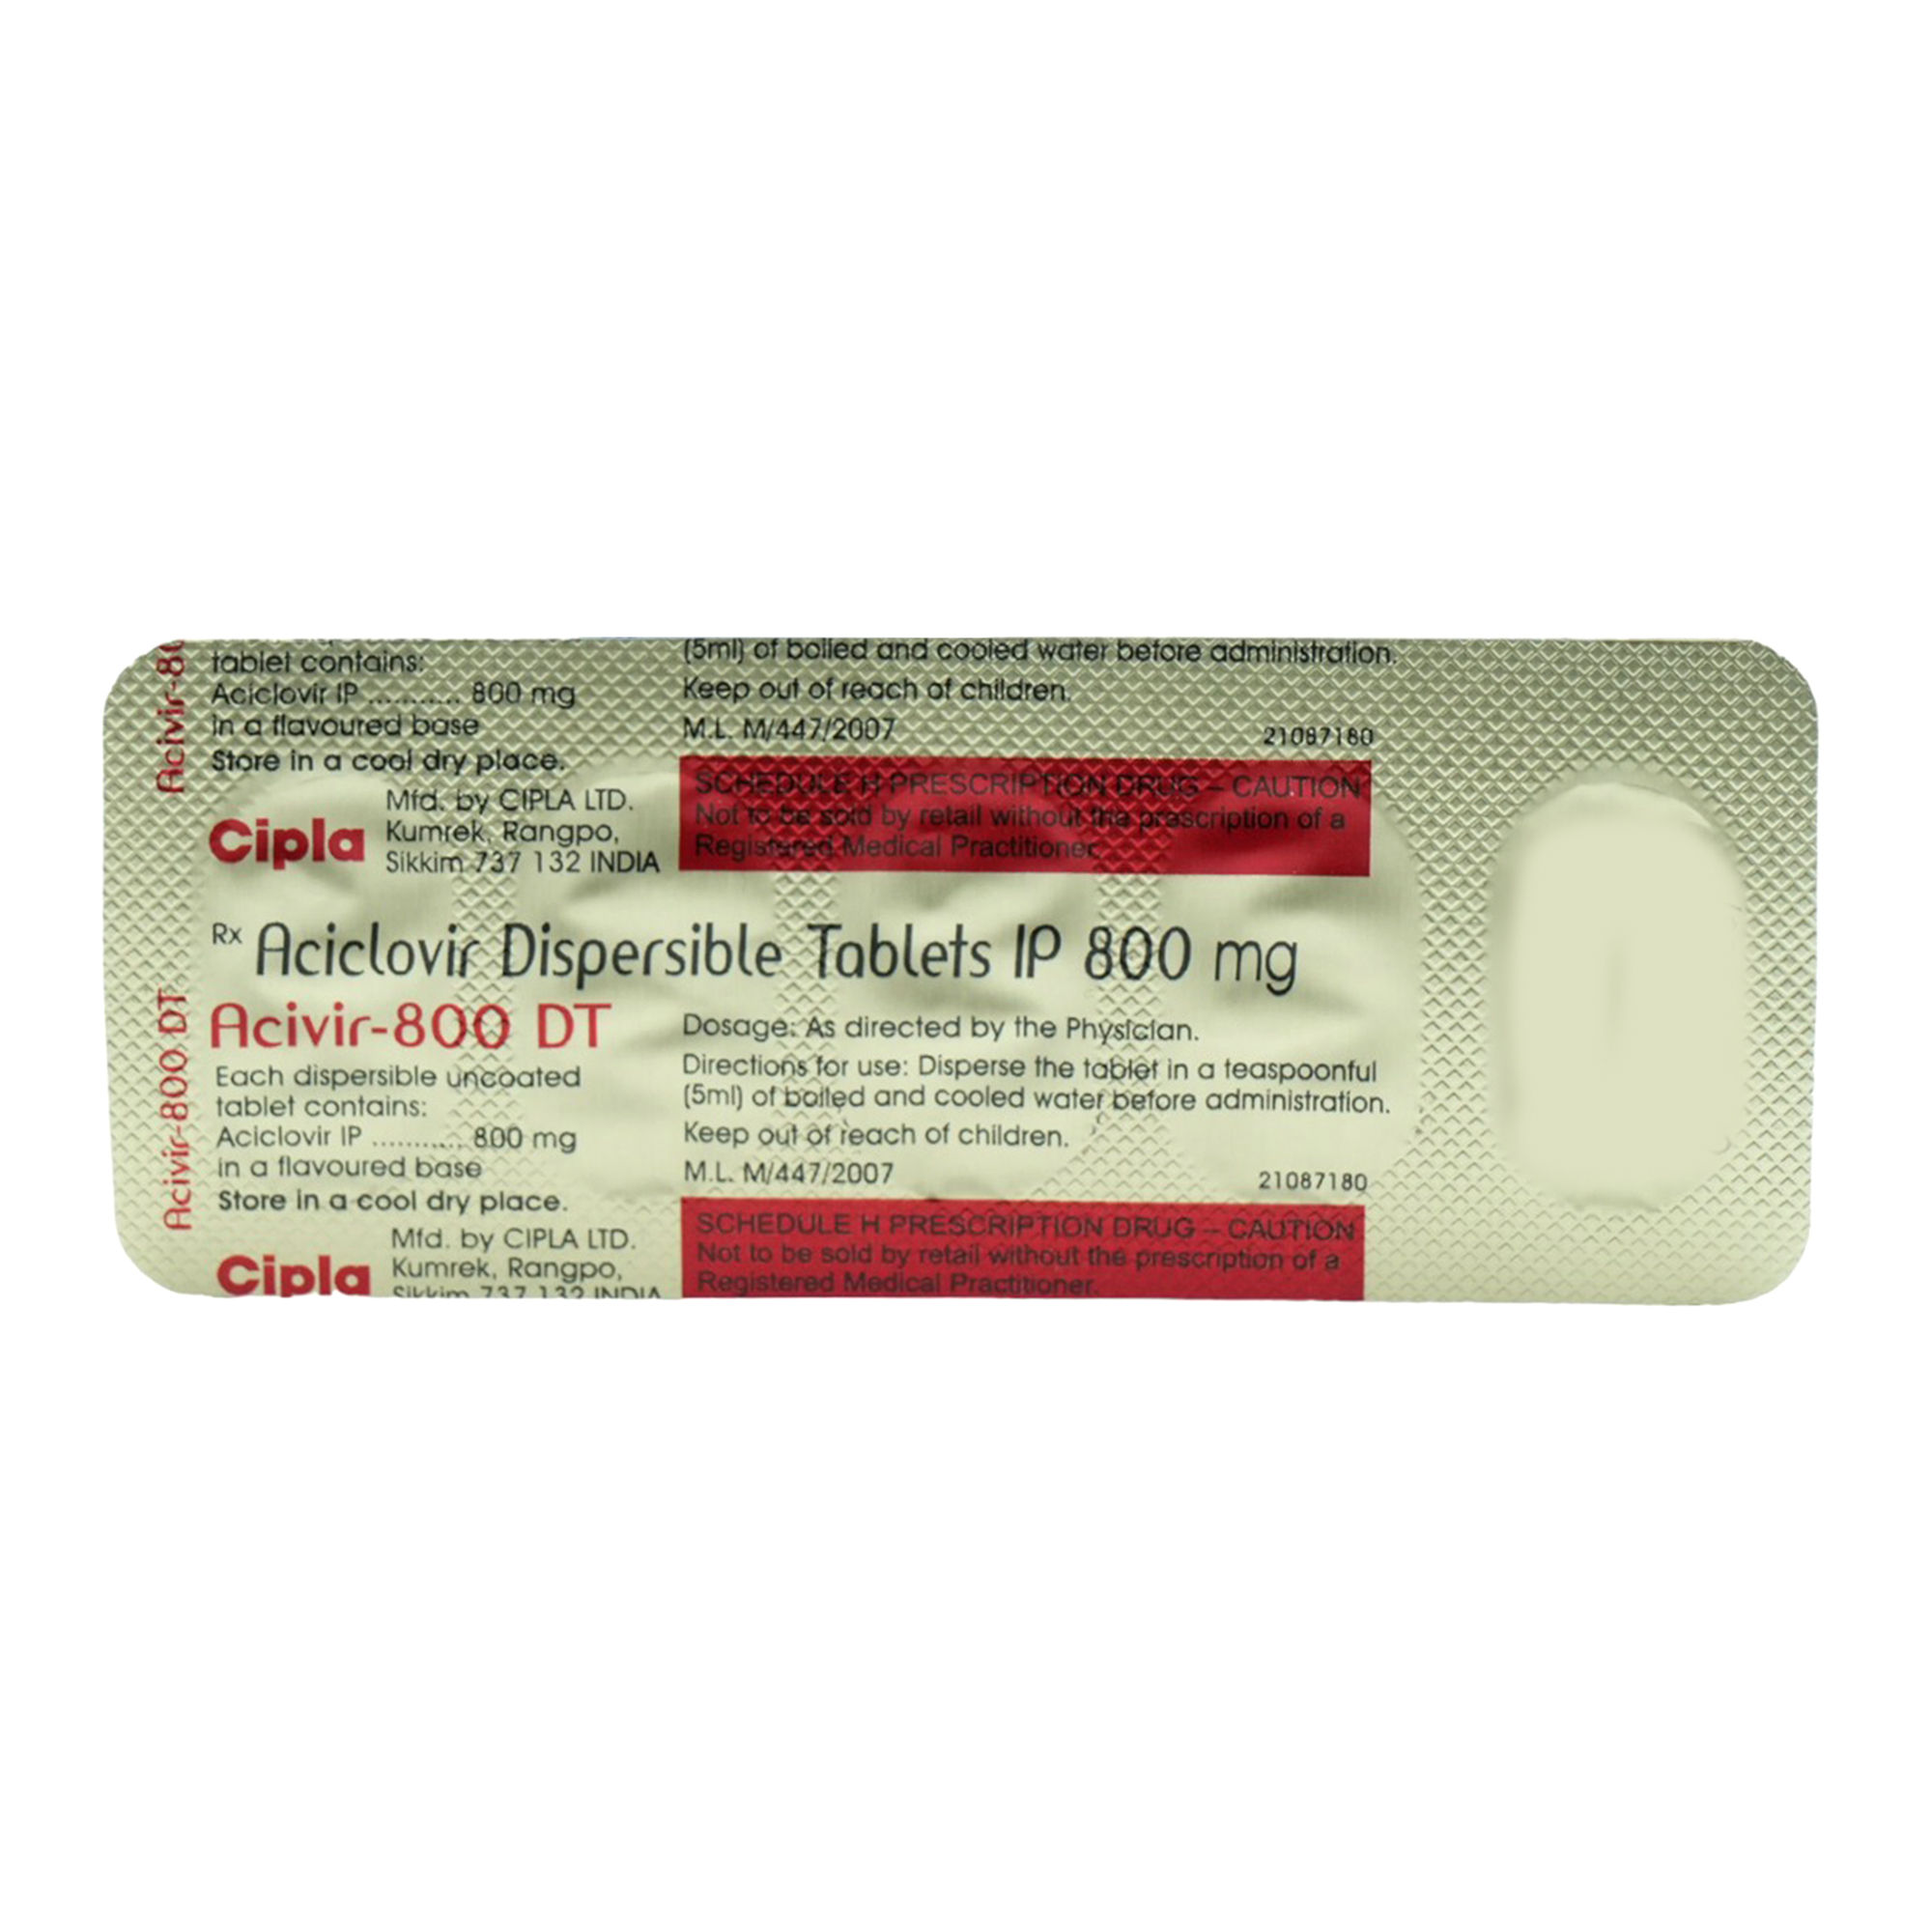

Aciclovir ACV, also known as acyclovir, 3 is an antiviral medication. Common side effects include nausea and diarrhea. |

Acyclovir Mg Tablets Certifications: Fda. |

Aciclovir also known as Acyclovir is one of the most commonly used antiviral medications to treat herpes simplex viruses, including genital herpes herpes simplex strain 2, HSV-2 and cold sores herpes simplex strain 1, HSV It also treats varicella zoster virus VZV, herpes zoster, which causes chickenpox and shingles. |